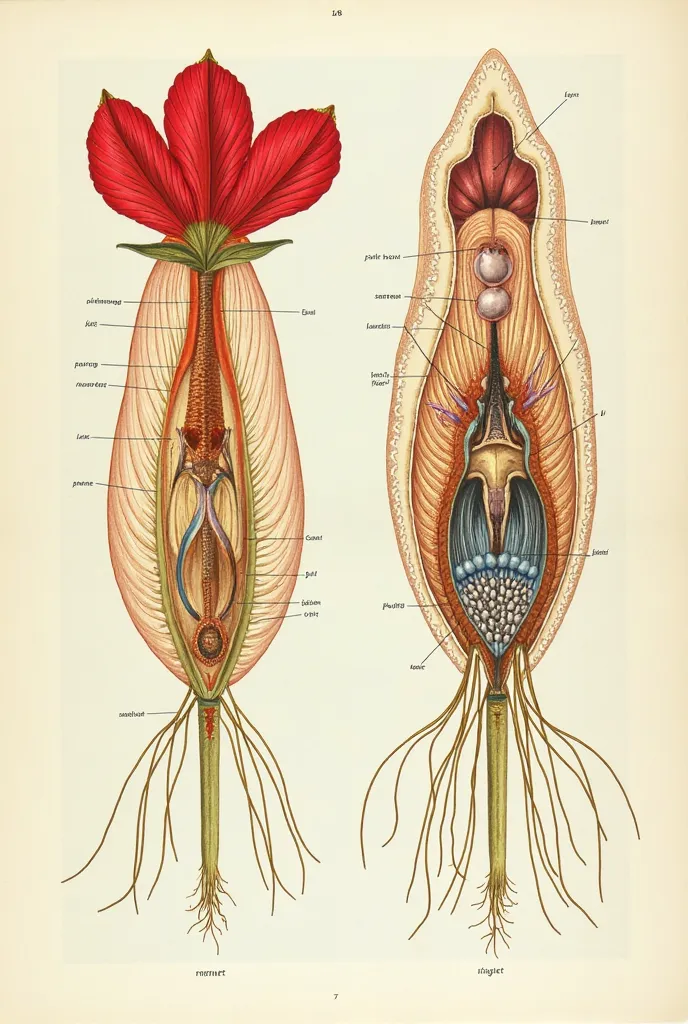

A diagram of the anatomy of the human body

Realice un dibujo de la piel. Coloque las siguientes referencias: Epidermis Fermis Hypodermis Keratinized squamous stratified epithelium Hair Sebaceous gland Sweat gland Pilo erector muscle Connective tissue Blood vessels Nerves Adipocytes

Epidermis Fermis Hypodermis Keratinized squamous stratified epithelium Hair Sebaceous gland Sweat gland Pilo erector muscle Connective tissue Blood vessels Nerves Adipocytes